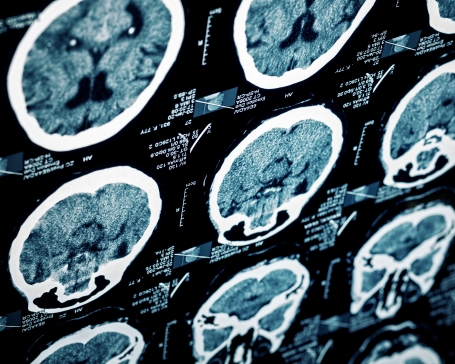

A stroke is always a medical emergency. If you recognise the signs of a stroke, call 000. A stroke is not a heart attack. It happens when the supply of blood to the brain is suddenly interrupted. Some strokes are fatal, while others cause permanent or temporary disability.

The longer a stroke remains untreated, the greater the chance of stroke-related brain damage. Emergency medical treatment soon after symptoms begin improves the chance of survival and successful rehabilitation.